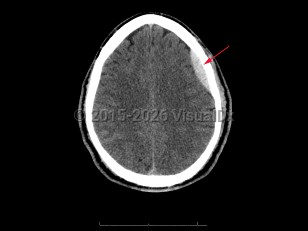

Subarachnoid hemorrhageSubarachnoid hemorrhage

Epidural intracranial hematomaEpidural intracranial hematoma

Subdural hematoma

Posterior fossa hematoma